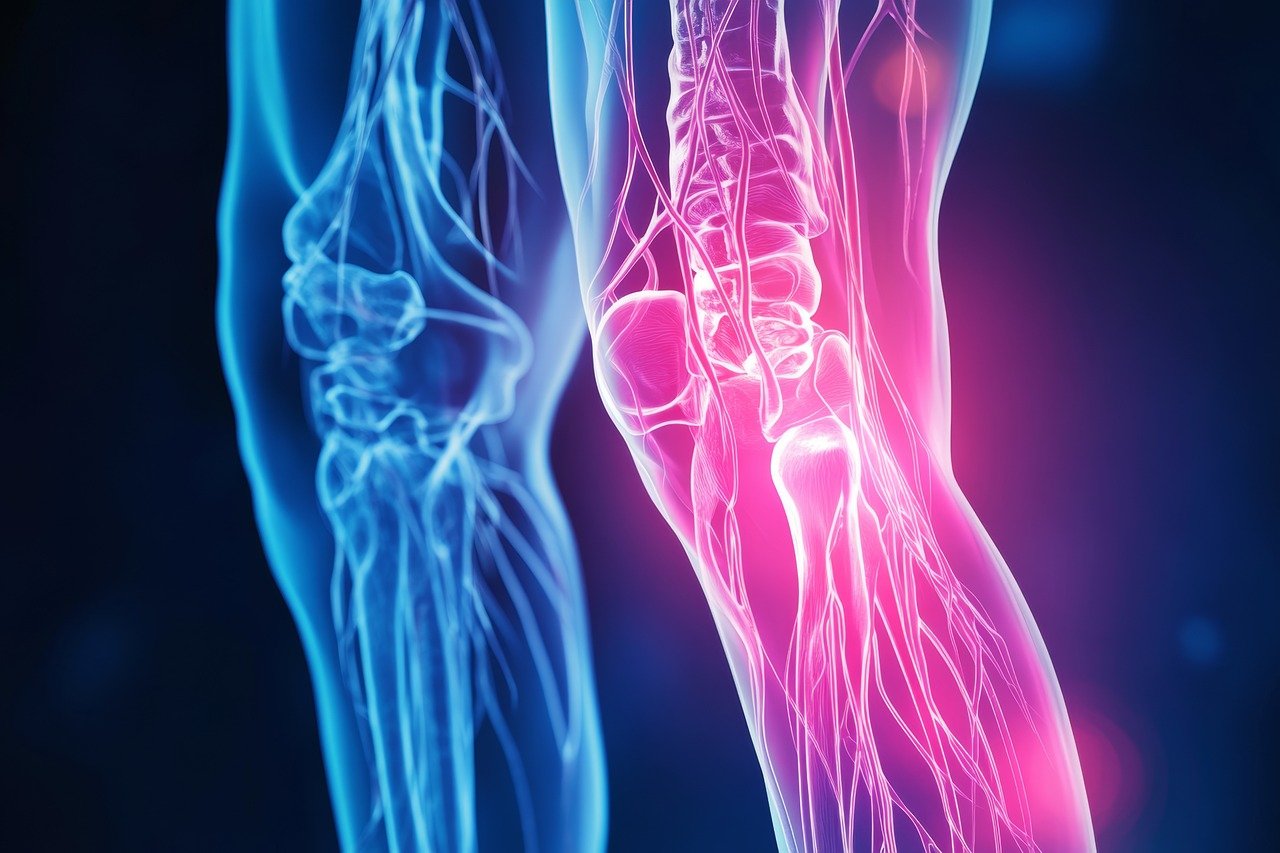

퇴행성 관절염은 주로 관절을 보호하는 연골의 퇴화로 인해 발생합니다.

연골은 뼈와 뼈 사이의 완충작용을 하며, 관절이 부드럽게 움직일 수 있도록 돕는 역할을 합니다.

하지만 연골이 손상되거나 얇아지면 뼈끼리 맞닿아 마찰이 발생하게 되고, 이는 염증과 통증을 유발합니다.

이러한 연골의 퇴화는 여러 가지 요인에 의해 촉진될 수 있습니다.